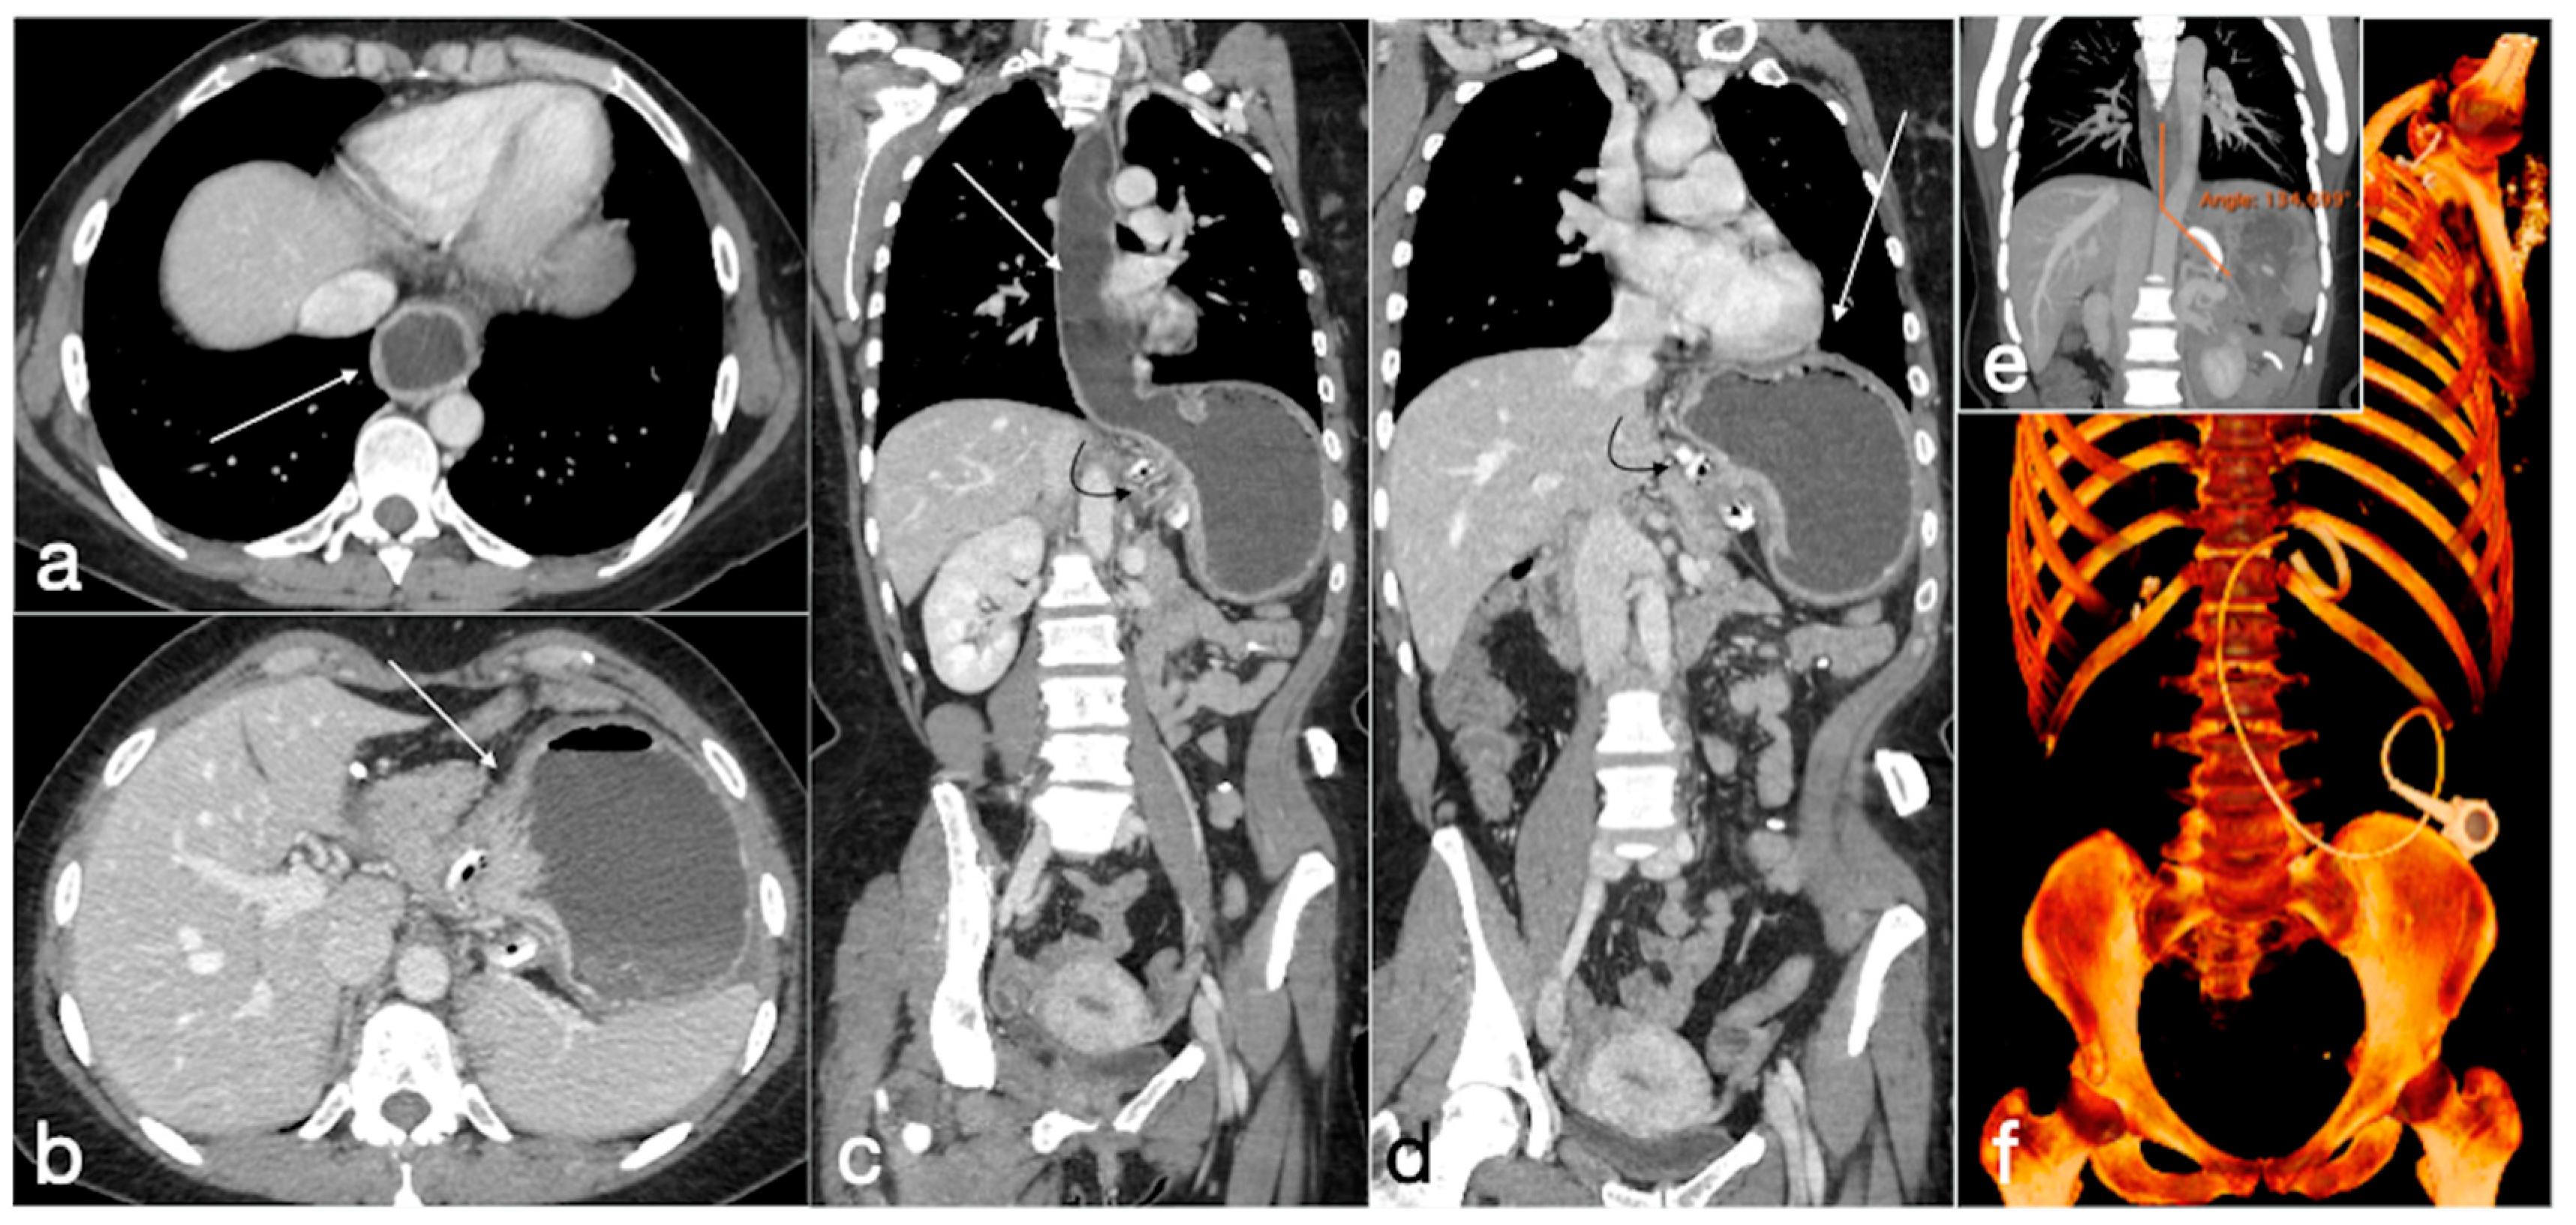

Figure 10. Gastric band slippage with gastric obstruction. A 40-year-old female with known gastric banding was complaining of abdominal pain and vomiting. There is dilatation of the esophagus (a, axial view, arrow) and of the gastric lumen proximal to the gastric banding (b, axial view, arrow). These findings are best seen in the coronal views (c,d, esophagus and stomach, straight arrows; gastric banding curved arrows). In (e) is shown the phi angle, excessively wide (134,699°), and in (f) the volume rendering reconstruction in which the excessive angulation of the device is clearly seen.